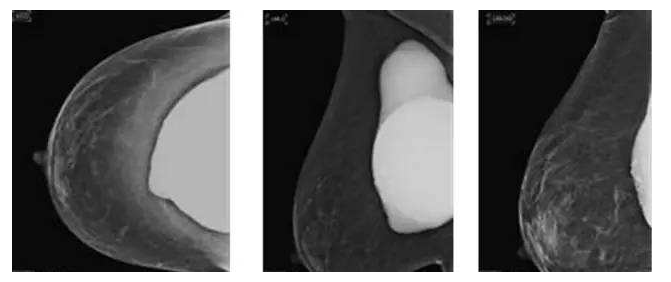

假体隆胸10年后将面临什么样的问题?

假体隆胸手术发展至今已有几十年历程,随之时代的发展,医学的进步,现代隆胸技术在不断升级,假体质量也在不断提高。现代信息的广泛传播,也让受众对于隆胸手术的了解全面化。一台成功的隆胸手术可以维持10年的时间,那么为什么是10年成为了隆胸的关键时期?10年后隆胸的人会面临怎样的问题?

假体隆胸没有终身性的理论,并不代表它就真的不能终身,只是出于健康考虑,我们需要在10后将假体可能存在的、不可预见的问题更加以关注。所以无论是专家、还是假体厂商对于假体的寿命都无法给予准确的答案。

置入假体在一定时间内可能出现老化现象,所以专家建议平均8-12年更换一次假体为宜,进口的硅胶假体维持时间会更长到10-20年,甚至更久。

因为假体质量不同、医生操作方式不同、个人体质存在差异,所以具体的存放时间无法被预估。所以假体隆胸10年后,应每年进行B超、核磁共振检查,以确保假体的完整性和安全性,排除并发症,如遇问题,可尽早进行处理。

假体老化最常出现的现象,比如囊壁钙化,渗漏,甚至破裂,还会随着人体组织的老化出现下垂问题。

囊壁钙化:硅胶假体在胸部存放时间过长,在硅胶和自身组织包膜之间,就有可能形成钙化沉淀。轻微的钙化不会对人体造成伤害,无需在意。但如果钙化出现较大的结块,而且集中出现在假体周围,便需要做组织取出或手术。

假体渗漏、破裂:囊膜皱褶经反复运动而老化破裂,后期渗漏或破裂,有纤维囊挛缩或急性炎症现象。假体破裂的发生率虽然很低,当假体出现明显的手感变化,形态的变化,那么这个时候就可能出现了假体的破裂,如果出现假体破裂就需要置换假体。

假体松弛下垂

如果出现假体隆胸变软下垂的问题可能是假体置入层次的问题,假体如果是放在胸部腺体下,它会随着自体的胸部往下垂而一起下垂,如果假体放在胸大肌下,那么就会出现腺体往下走,而假体不往下走,就有可能形成四个胸部的情况。

最后提醒大家,一般情况下假体维持10-20年基本没有问题,不必对此过于忧虑。时常观察胸部大小变化,手感软硬程度,每年做好定期检查即可。